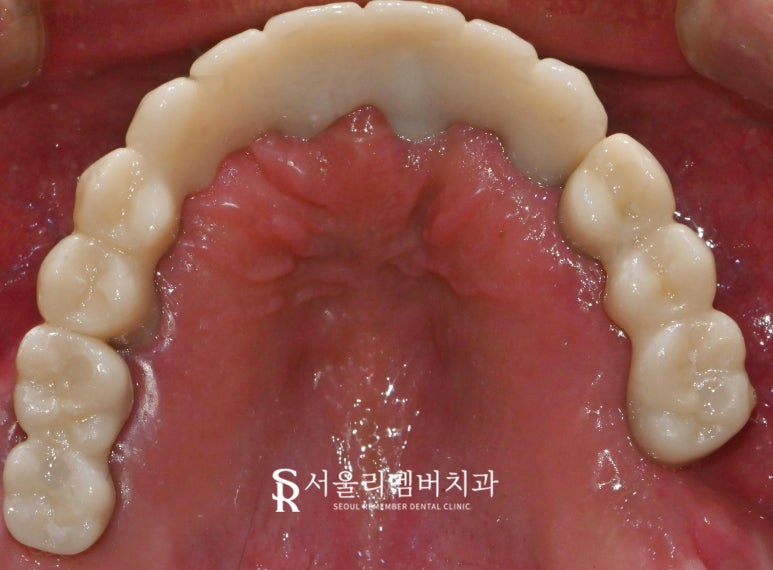

- 최종 결과

자 그럼 완성된 환자의 구강 모습을 확인해 볼까요?

새롭게 바뀐 구강 환경으로 이제

더는 아파하지 않으실 거라 생각되니

마음이 한결 편안해지네요.

환자께서도 확 달라진 모습에

계속 거울을 보며 말씀하셨습니다.

"원장님 덕분에 못 먹었던 음식들

먹게 될 수 있을 것 같아요.

너무 감사합니다!"